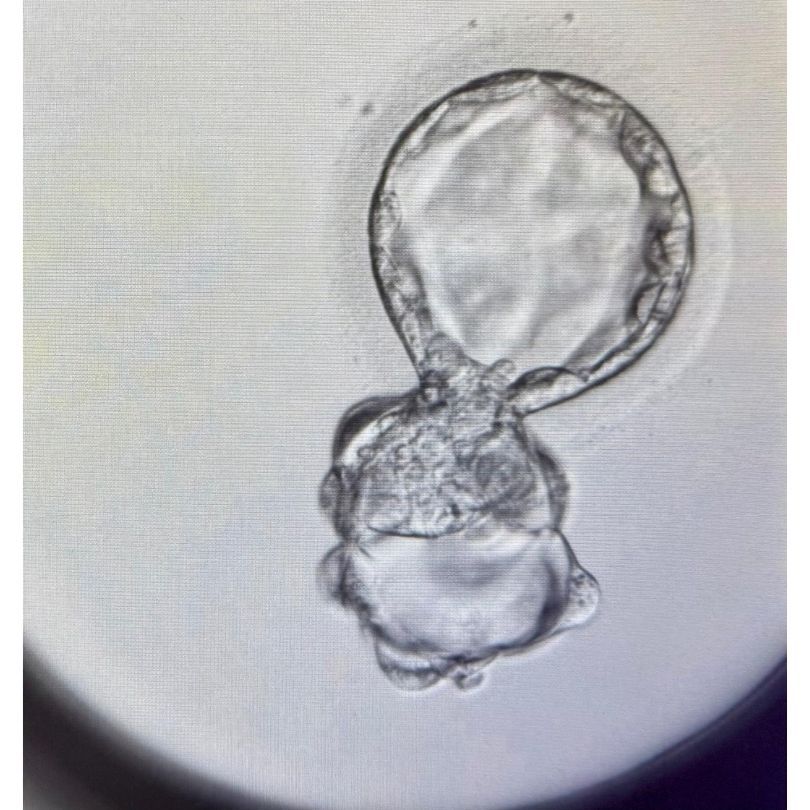

Foto e video